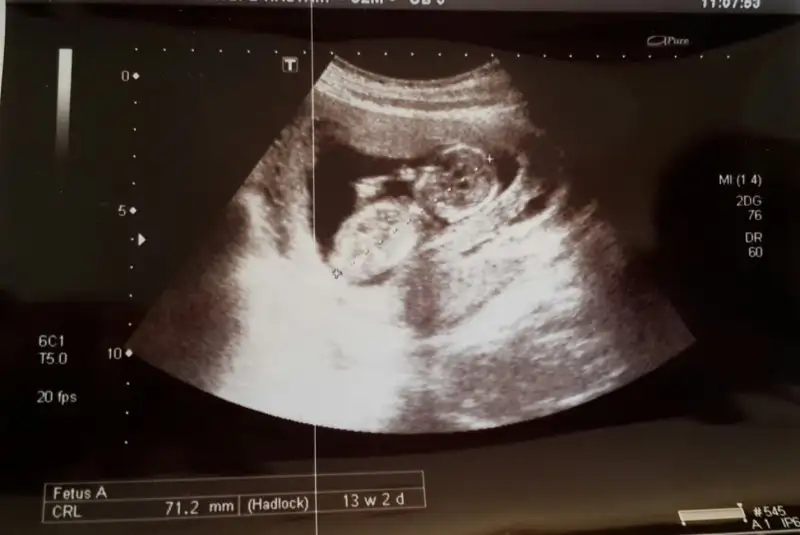

İlki cumartesi aldım ikincisi bugüne ait. Bugünkü çok karanlık.

cumartesi günkü yaptı erkek gibi dedi. ama bugünkü çok da uğraşmadı döndürmek için falan göstermiyor dedi. bu cumartesi tekrar kendi doktoruma gideceğim için de ısrar etmedim.Maşallah bebişe:) ben hiç anlamam ama 2. Resimde sanki baya erkek çocuğu görüyorum yaDr Bi yorum yaptı mı